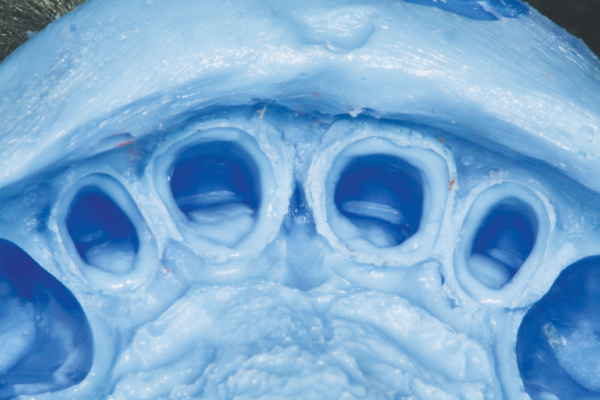

The quadrant impression tray must be wide enough, yet adaptable to fit a myriad of quadrant lengths, widths, and tooth position scenarios. As such, the adjusted tray has to be comfortable enough for the patient to endure the setting time. There can be no painful hard or soft tissue impingement that may alter the patient’s ability to occlude in the appropriate matter. The tray must also be stable throughout the impression procedure, regardless of the occlusal forces placed on it through the patient closing into the impression material, as well as during the removal of the impression from the mouth. Any distortion, no matter how slight, may result in an ill-fitting restoration requiring adjustments in order to be functional. The ideal tray will hold the tray material securely so that it does not pull away from the tray upon removal from the mouth. Tray stability throughout the impression procedure is paramount to a highly accurate final impression.

One must be careful when utilizing a plastic tray for a final dual-arch impression. Many plastic trays have a narrow occlusal table and are elastic in nature. This may lead to hard tissue interference from a tooth that is either in linguo or bucco-version. The interference will decrease the accuracy of the bite registration element of the dual-arch impression. Additionally, the mere force of the patient biting into the tray material, with or without hard or soft tissue impingement, may cause the tray to twist or flex. Upon removal from the mouth, the plastic tray will instinctively return to its original shape. This will lead to distortion of the final impression that is indiscernible to the naked eye. Only the rigidity of the set tray material may keep this from happening.

The tray material chosen for the dual-arch technique is also vital for providing the laboratory with a stable, accurate impression. Dual-arch impressions differ from full-arch impressions in that a great deal of dimensional stability of the impression depends on the rigidity or hardness of the tray material versus the metal or plastic full-arch tray. The best choice would be a tray material designed to be both as rigid as possible, yet displaying the ideal flow that does not displace the light body from the preparation. For optimal dimensional stability, ensure that the upper and lower aspects of the tray material are actually connected buccal and lingually.